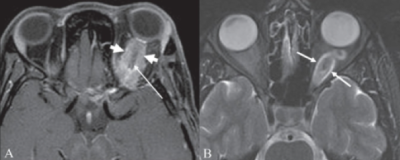

Optic pathway glioma can present with loss in visual acuity, color alterations, and visual field alterations so a visual field examination can be important for screening for these tumors[39]. However, these tests can be difficult to perform on young children and vision deficits only occur in less than 50% of patients. Magnetic resonance imaging (MRI) is the best diagnostic technique to observe optic pathway tumors[9]. Several studies have also demonstrated thinning of the retinal nerve fiber layer with OCT in patients affected with optic pathway tumors[25][46][47].

- ↑ Chavhan G. B., Shroff M. M., CC BY 2.0 <https://creativecommons.org/licenses/by/2.0>, via Wikimedia Commons https://commons.wikimedia.org/wiki/File:Optic_nerve_sheath_meningioma.png Accessed June 7, 2020.